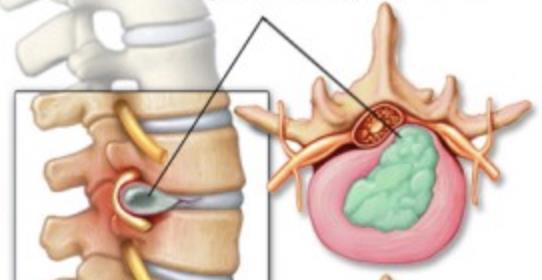

1. Hernias discales

¿Por qué se producen las hernias discales?

Las hernias discales pueden aparecer en todas las edades. No son características de la edad infantil, pero también se pueden ver en algunos casos. Si aparecen en el niño la causa es desconocida; en algunas ocasiones también pueden tener relación con un esfuerzo, un movimiento brusco que origine la rotura del anillo fibroso y la salida del disco con compresión del nervio (Fig 1).